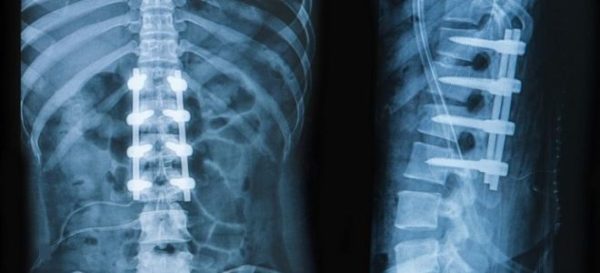

Для неврологов, травматологов и ортопедов важно использовать данный метод обследования, чтобы точно определить состояние своих пациентов. Рентгеновское исследование позволяет выявить грыжу позвоночника, сколиоз, различные микротравмы, нарушения костно-связочного аппарата (патологии здоровой стопы), переломы (лучезапястного сустава) и многое другое.

Интерпретацией изображений занимается только медицинский специалист. Именно он способен заметить даже мельчайшие проявления заболевания. Однако обычный человек в определенных ситуациях может заметить проблему на снимке и понять, что что-то не так с его организмом. Например, при рентгеновском обследовании позвоночника даже сам пациент может увидеть сколиоз или переломы.

Рентгенография позвоночника может быть назначена для выявления переломов, деформаций, дислокаций, а также для диагностики остеохондроза, сколиоза, аномалий развития позвоночника и других патологий.